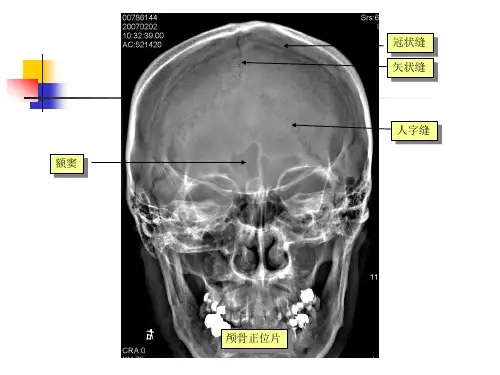

一.X线检查适应征与局限性⒈适应征:对颅骨的显示是重要的检查方法。

特别对怀疑侵犯颅骨的病变、颅骨的先天性畸形等病变X线检查有很大的价值。

⒉局限性:中枢神经系统X线检查的作用正在被逐渐减弱,对颅内病变的显示明显不如其他影像学检查方法,由于脑组织与脑脊液的密度相似,除钙化外单凭头颅平片不能进行明确诊断。